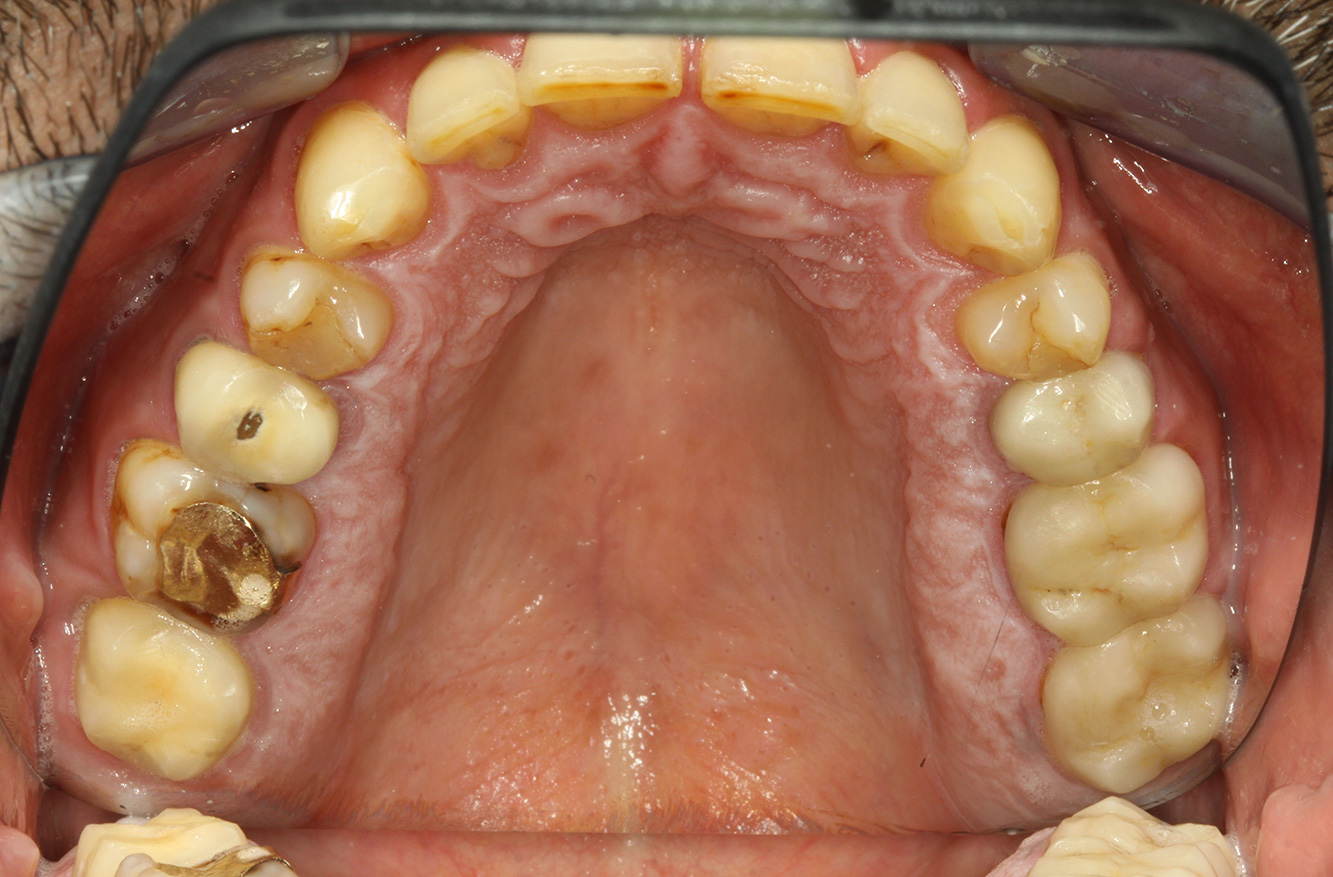

The endocarditis patient with active caries lesions*

The patient is 39 years old and has previously undergone aortic valve replacement due to valve failure and endocarditis. ASS 100 is taken regularly as an anticoagulant. In terms of lifestyle, the patient’s diet is classified as caries-promoting due to the regular consumption of sugary foods and the fact that six to seven meals are consumed daily. The patient’s oral health indicates a moderate risk of caries, with active lesions. The risk of periodontitis is low, but gingivitis is present. The following recommendations are made for prophylactic treatment.

No specific instrument recommendations can be determined for the prophylaxis session. Targeted application of air and rotary polishing can be used to gently reduce plaque and stains on the restoration edges, and to reduce recolonization niches for cariogenic bacteria (19).

Fluoridation is recommended to further support the prevention of caries, and especially to prevent new formation around the restoration edges, and to seal the root surfaces. Both of these measures can reduce the teeth’s sensitivity to temperature.